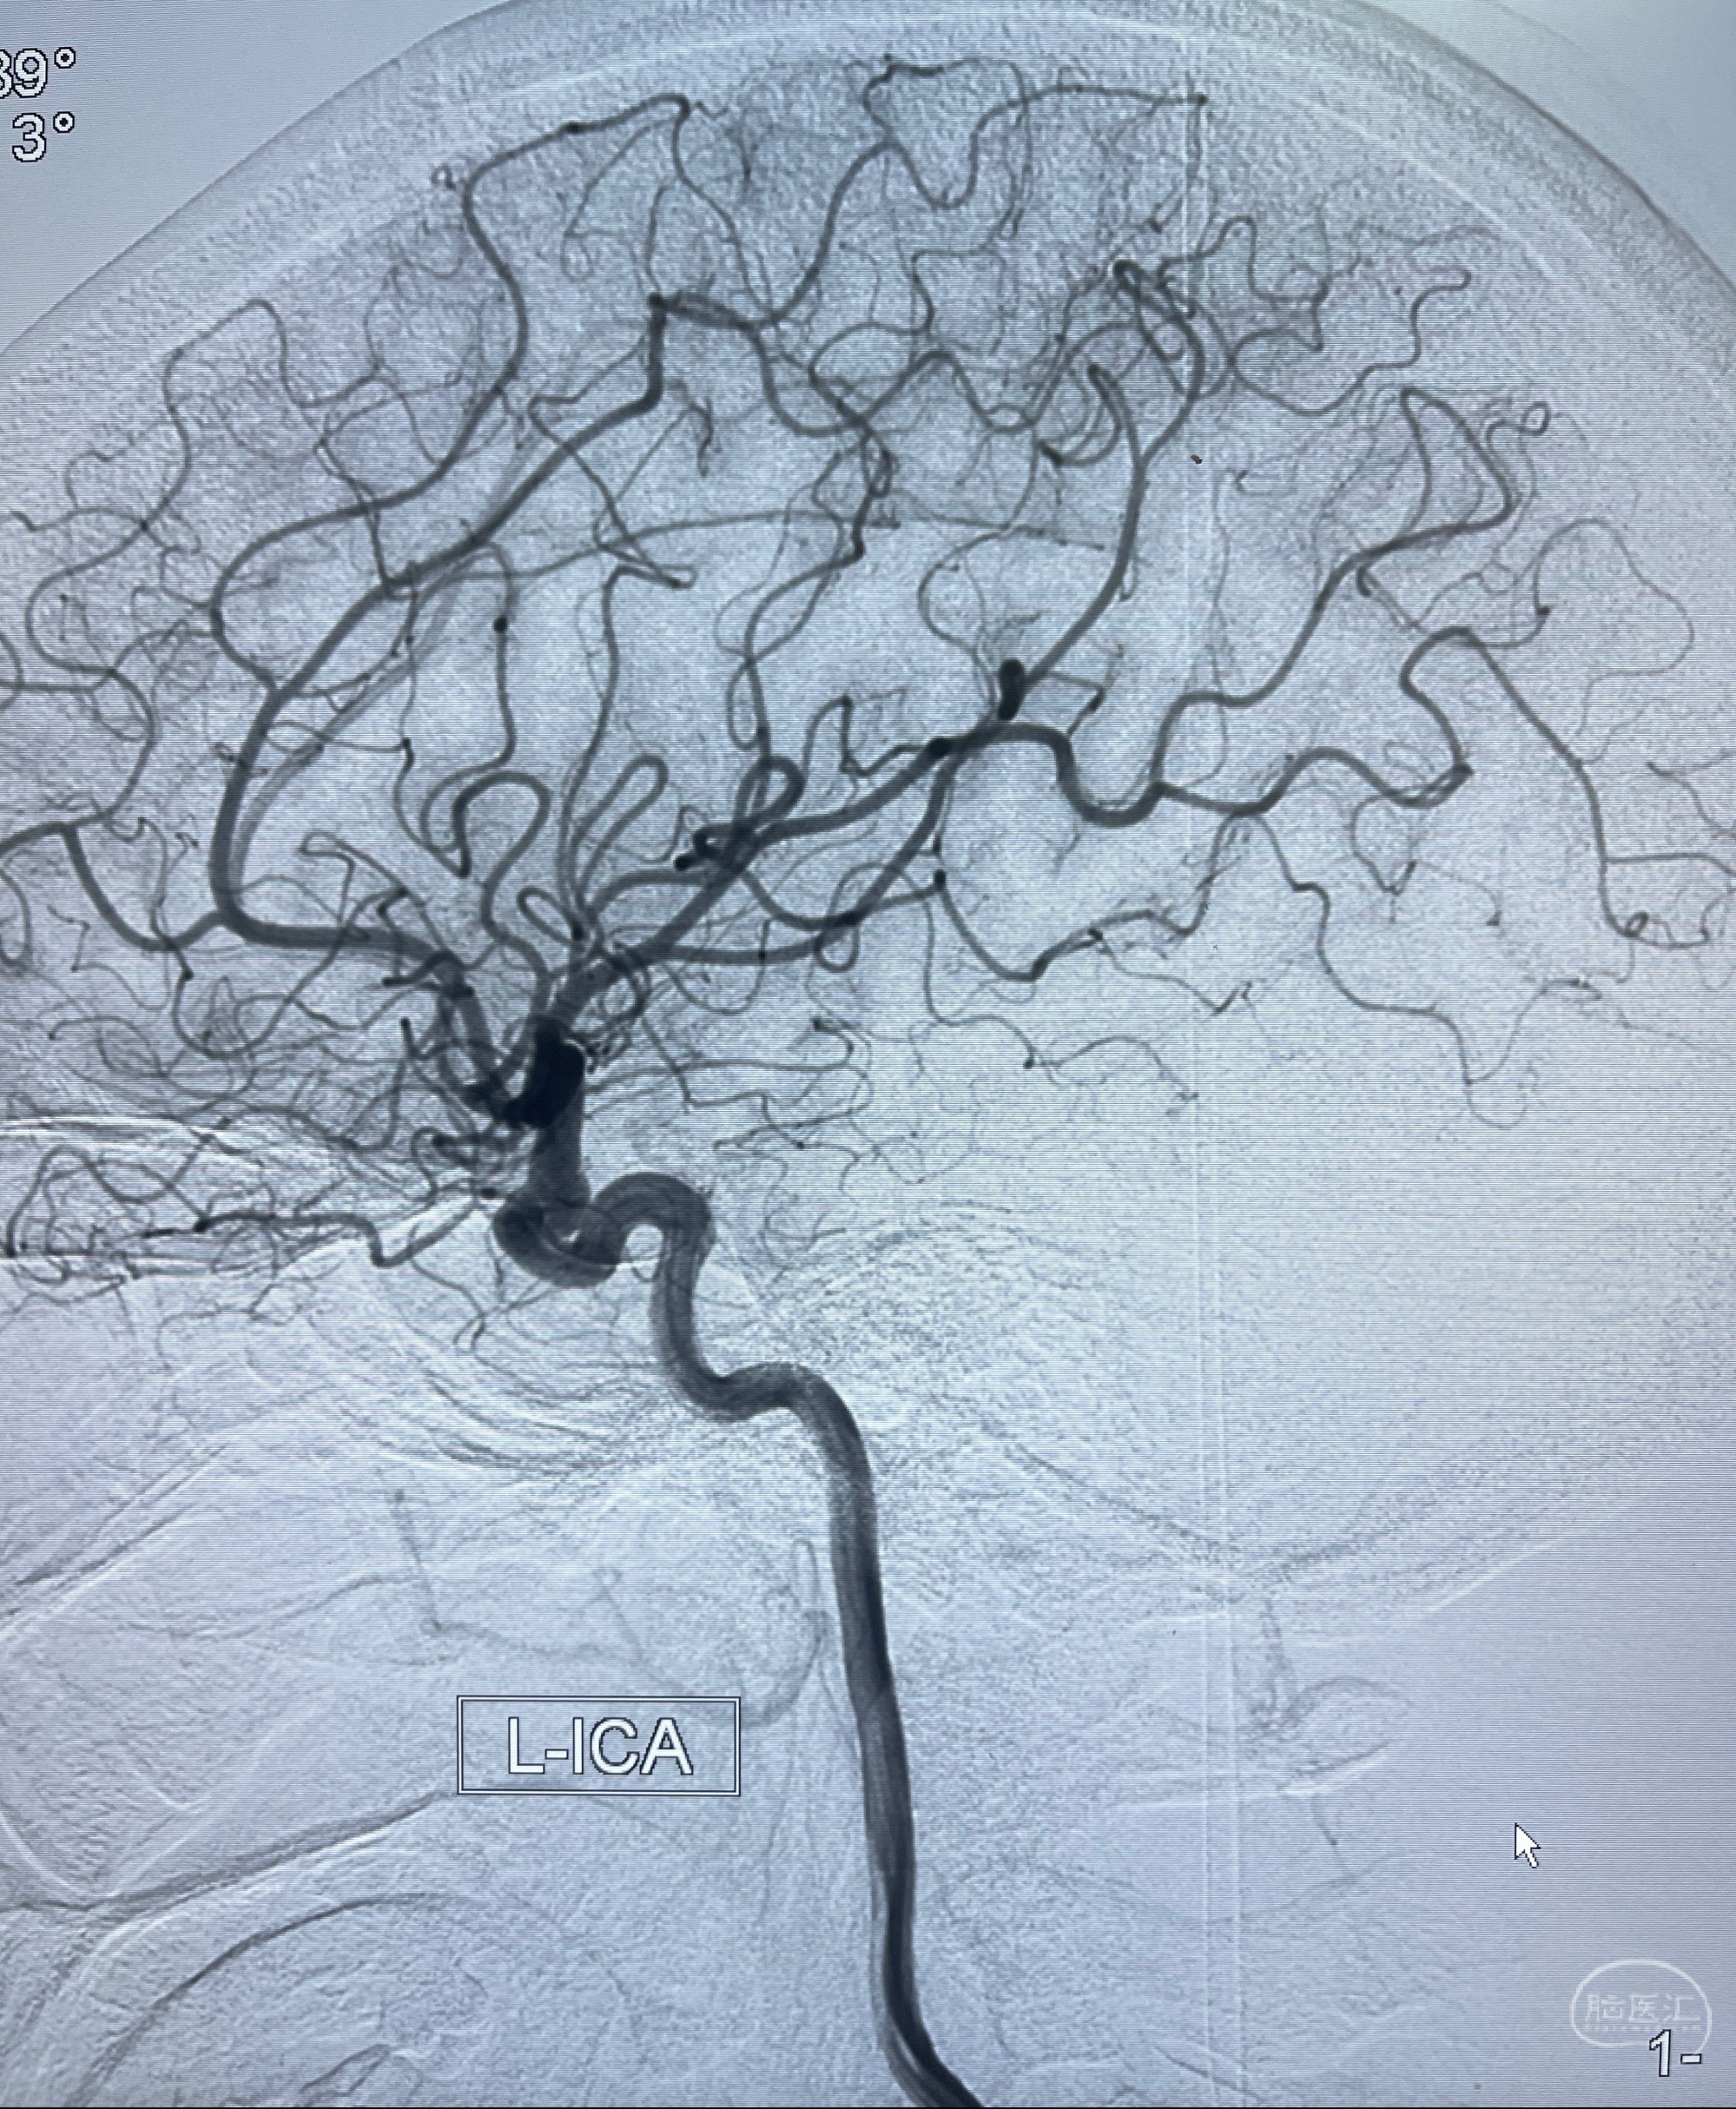

2023-07-27全脑血管造影:双侧颈内动脉眼动脉段动脉瘤,右侧较大

2023-08-01全麻下行双侧颈眼动脉瘤支架辅助栓塞

- pipeling4.5-20mm

- pipeline 4.0-20mm